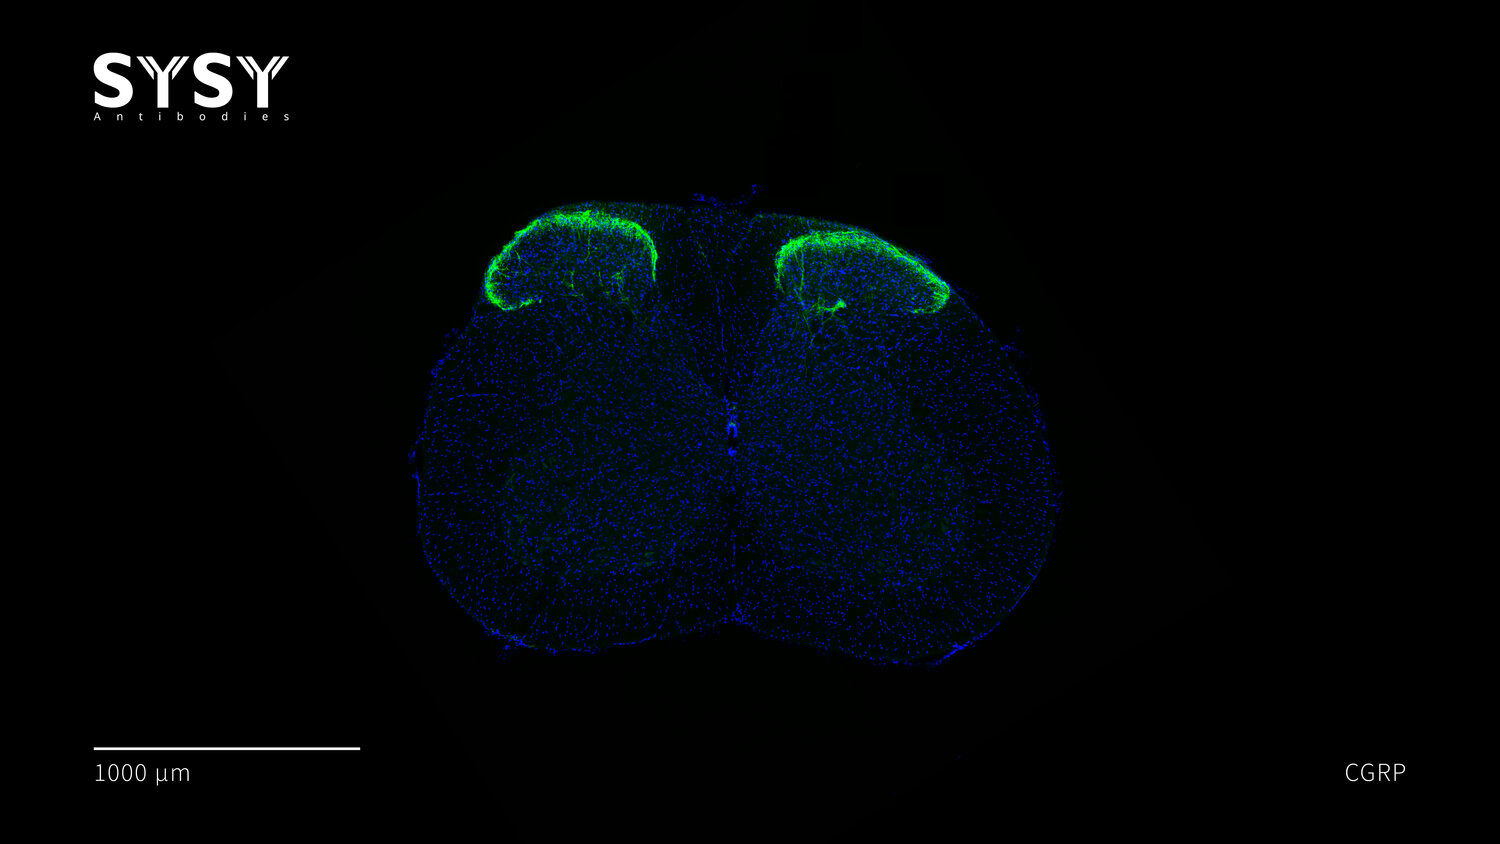

CGRP

Indirect immunostaining of a formaldehyde fixed mouse spinal chord section with guinea pig anti-CGRP antibody (cat. no. 414 004, dilution 1 : 500).